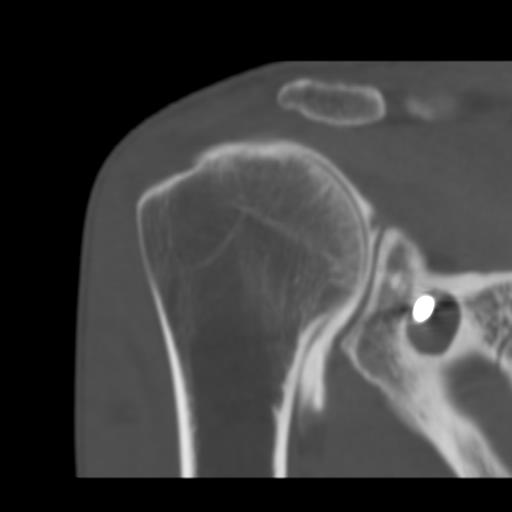

J’ ai dû me faire opérer, oh pas de grand chose, une luxation d’ épaule mais le chirurgien s’ est complètement planté, j’ étais dans un sale état quand enfin j’ ai rencontré un médecin disposé à m’ aider, on me l’ avait bien caché, il a cependant dû me réopérer trois fois.

Les hôpitaux publics me redirigeaient toujours vers l’ établissement qui m’ a raté, le service concerné prétendait que tout allait bien, que la greffe n’ avait pas prise mais qu’ elle ne bougeait pas ( examen réalisé au papier calque). Je repartais avec des ordonnances contre la douleur de plus en plus gonflées, un jour on m’ a demandé si c’ était pour un cheval lorsque j’ ai voulu reproduire l’ une d’ elles.

J’ ai tenté de porter plainte contre l’ hôpital, il parait que ça ne se fait pas, ça m’ a coûté des nerfs et pas mal d’ argent pour des rapports qui informent que la greffe était mal positionné, qu’ elle ne pouvait pas prendre mais que l’ on ne peut cependant pas considérer qu’ il s’ agit d’ une erreur. De quoi s’ agit t’ il alors ? D’ une expérience ? Est ce que j’ ai servi de cobaye ? Je n’ en saurai jamais plus, le dernier expert m’ a conseillé d’ abandonner, que j’ allais me noyer dans cette affaire.